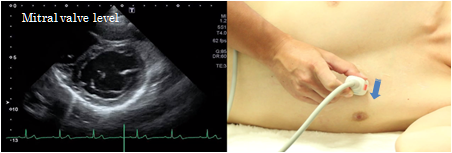

Mitral orifice level

The mitral orifice level of the short axis view of the left ventricle depicts the mitral valve with a large anterior cusp in the front and a small and wide posterior cusp at the backside of the image. The anterior commissure is located on the right side of the screen and the posterior commissure on the left side. This view is used to determine the site of mitral valve prolapse and measure the mitral valve area in case of mitral valve stenosis.